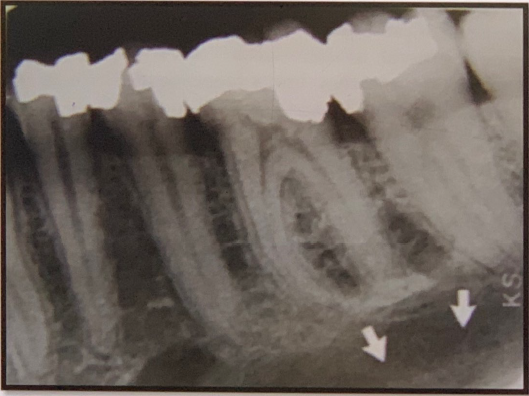

94. what does arrow show?

Submandibular Gland Fossa a bone depression on the lingual surface of the mandibular body, immediately below the mylohyoid ridge in the molar area. often appears as a radiolucent area with the sparse trabecular pattern